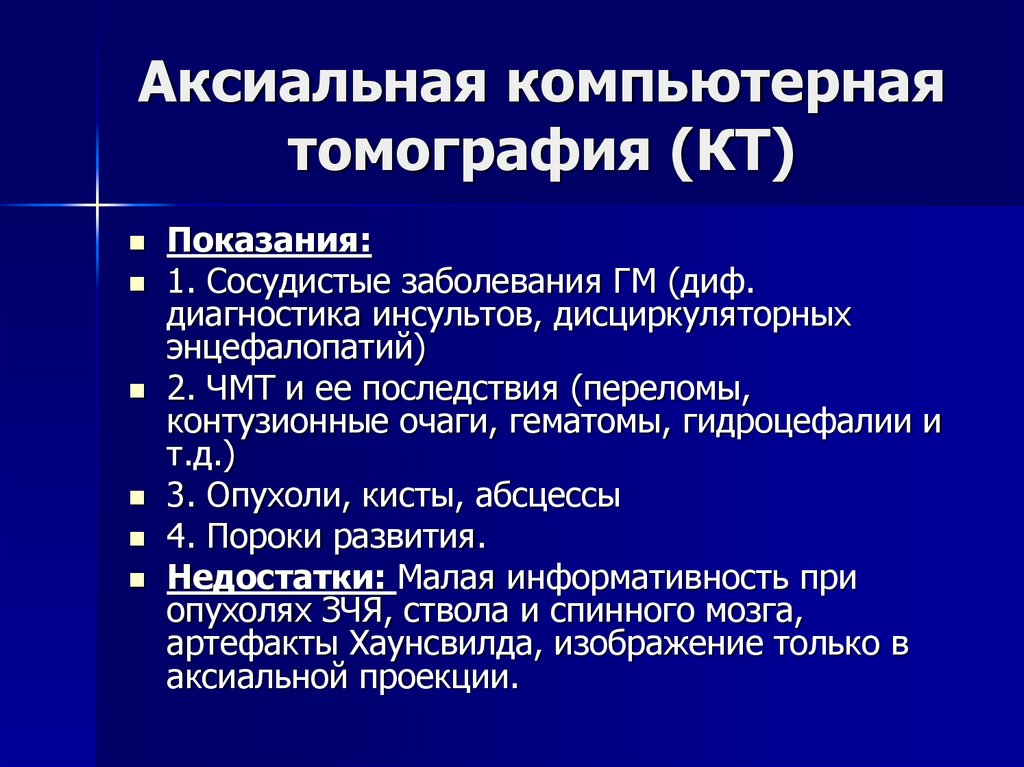

Компьютерная томография в неврологии презентация - 86 фото